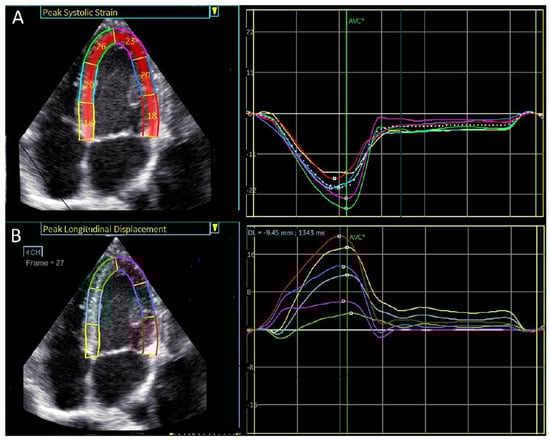

Regional longitudinal displacement was highest in the basal segments and lowest in the apical segments, 17.6 ± 3.5 vs. 11.5 ± 2.9 vs. 4.22 ± 1.7 mm in basal, mid, and apical segments, respectively, p < 0.000001 (Table 2, Figure 2). In contrast, the lowest longitudinal strain was observed in the basal left ventricular segments, while the highest was found in the apex of the left ventricle, −16.3 ± 4.7 vs. −19 ± 2.5 vs. −21.1 ± 4.6% in basal, mid, and apical segments, respectively, p < 0.000001, (Table 2, Figure 3).

An example of peak systolic regional longitudinal displacement and strain for a 27-year-old football player is shown in Figure 5A,B. In contrast to the peak systolic strain, which exhibits a basal-to-apical gradient, peak longitudinal displacement is highest in the basal segments and lowest in the apical segments, demonstrating a reversed basal-to-apical gradient.

Figure 3. Visual plot of regional longitudinal displacement and strain over the left ventricle across the healthy study population [Group 1]. (A) Regional peak systolic longitudinal displacement over the left ventricle is highest in the basal segments and lowest in the apical segments. (B) Regional peak systolic longitudinal strain is lowest in the basal segments and highest in the apical segments.

Figure 5. A visual plot of the normal peak longitudinal displacement and strain of 27-year-old football player. (A) Peak longitudinal displacement is highest in the basal segments and lowest in the apex. (B) Peak longitudinal strain is lowest in the basal segment and highest in the apex.